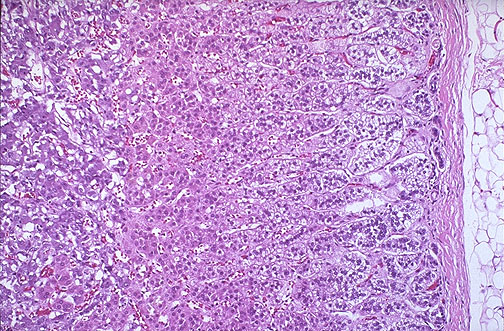

Normal adrenal gland, low power microscopic, with

capsule

at right and the

glomerulosa

, the

fasciculata

, and the

reticularis

layers of cortex extending down to the

medulla

at the left.